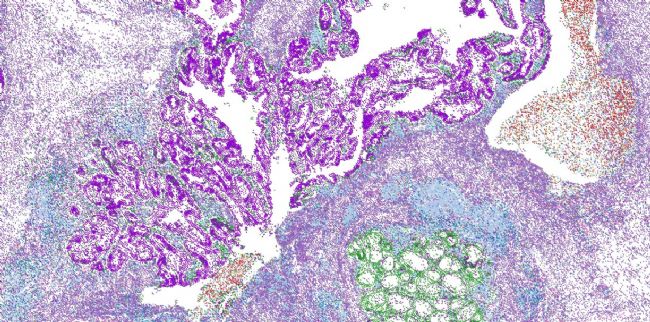

Visium HD空間分析鑒定出KRAS突變型結直腸癌樣本中的細胞組成。圖片來源:葉幼瓊實驗室

02 您在研究中為什么選擇空間轉錄組學?由于我們的多項研究使用了空間轉錄組學數據,我們甚至開發(fā)出計算工具Cottrazm用于空間腫瘤分析。該工具整合了空間轉錄組學數據、蘇木精-伊紅(H&E)組織學圖像中的形態(tài)學信息,以及單細胞轉錄組學數據。我們隨后用這些數據來勾勒腫瘤邊界以及腫瘤組織中的細胞“點”,進而揭示細胞類型特異性的基因表達特征。

最近,我們還利用腫瘤空間組學數據來分析泛癌種微環(huán)境特征。該項目致力于將功能富集的差異表達基因定位在特定腫瘤結構,解析TME的細胞組成,鑒定細胞類型特異性基因表達特征,并表征細胞間相互作用。根據這些,我們開發(fā)出一個名為SpatialTME的用戶友好數據庫,支持用戶搜索,可視化下載結果。